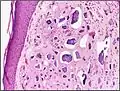

Micrograph of calcinosis cutis. The calcification is purple (bottom of image). H&E stain.